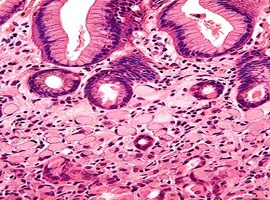

Signet Ring Cell Carcinoma Presenting as Terminal Ileitis: A Case Report

Volume 8, Issue 1

:

Read More